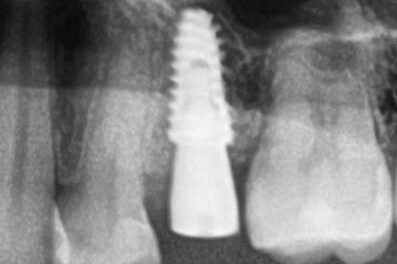

Специализация: терапия(эндодонтия), ортопедия, имплантология.